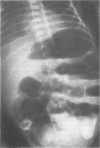

Antenatal appendicular perforation leading to localized meconium peritonitis and intestinal obstruction is reported in a premature neonate. The baby was successfully treated by a limited ileocaecal resection.